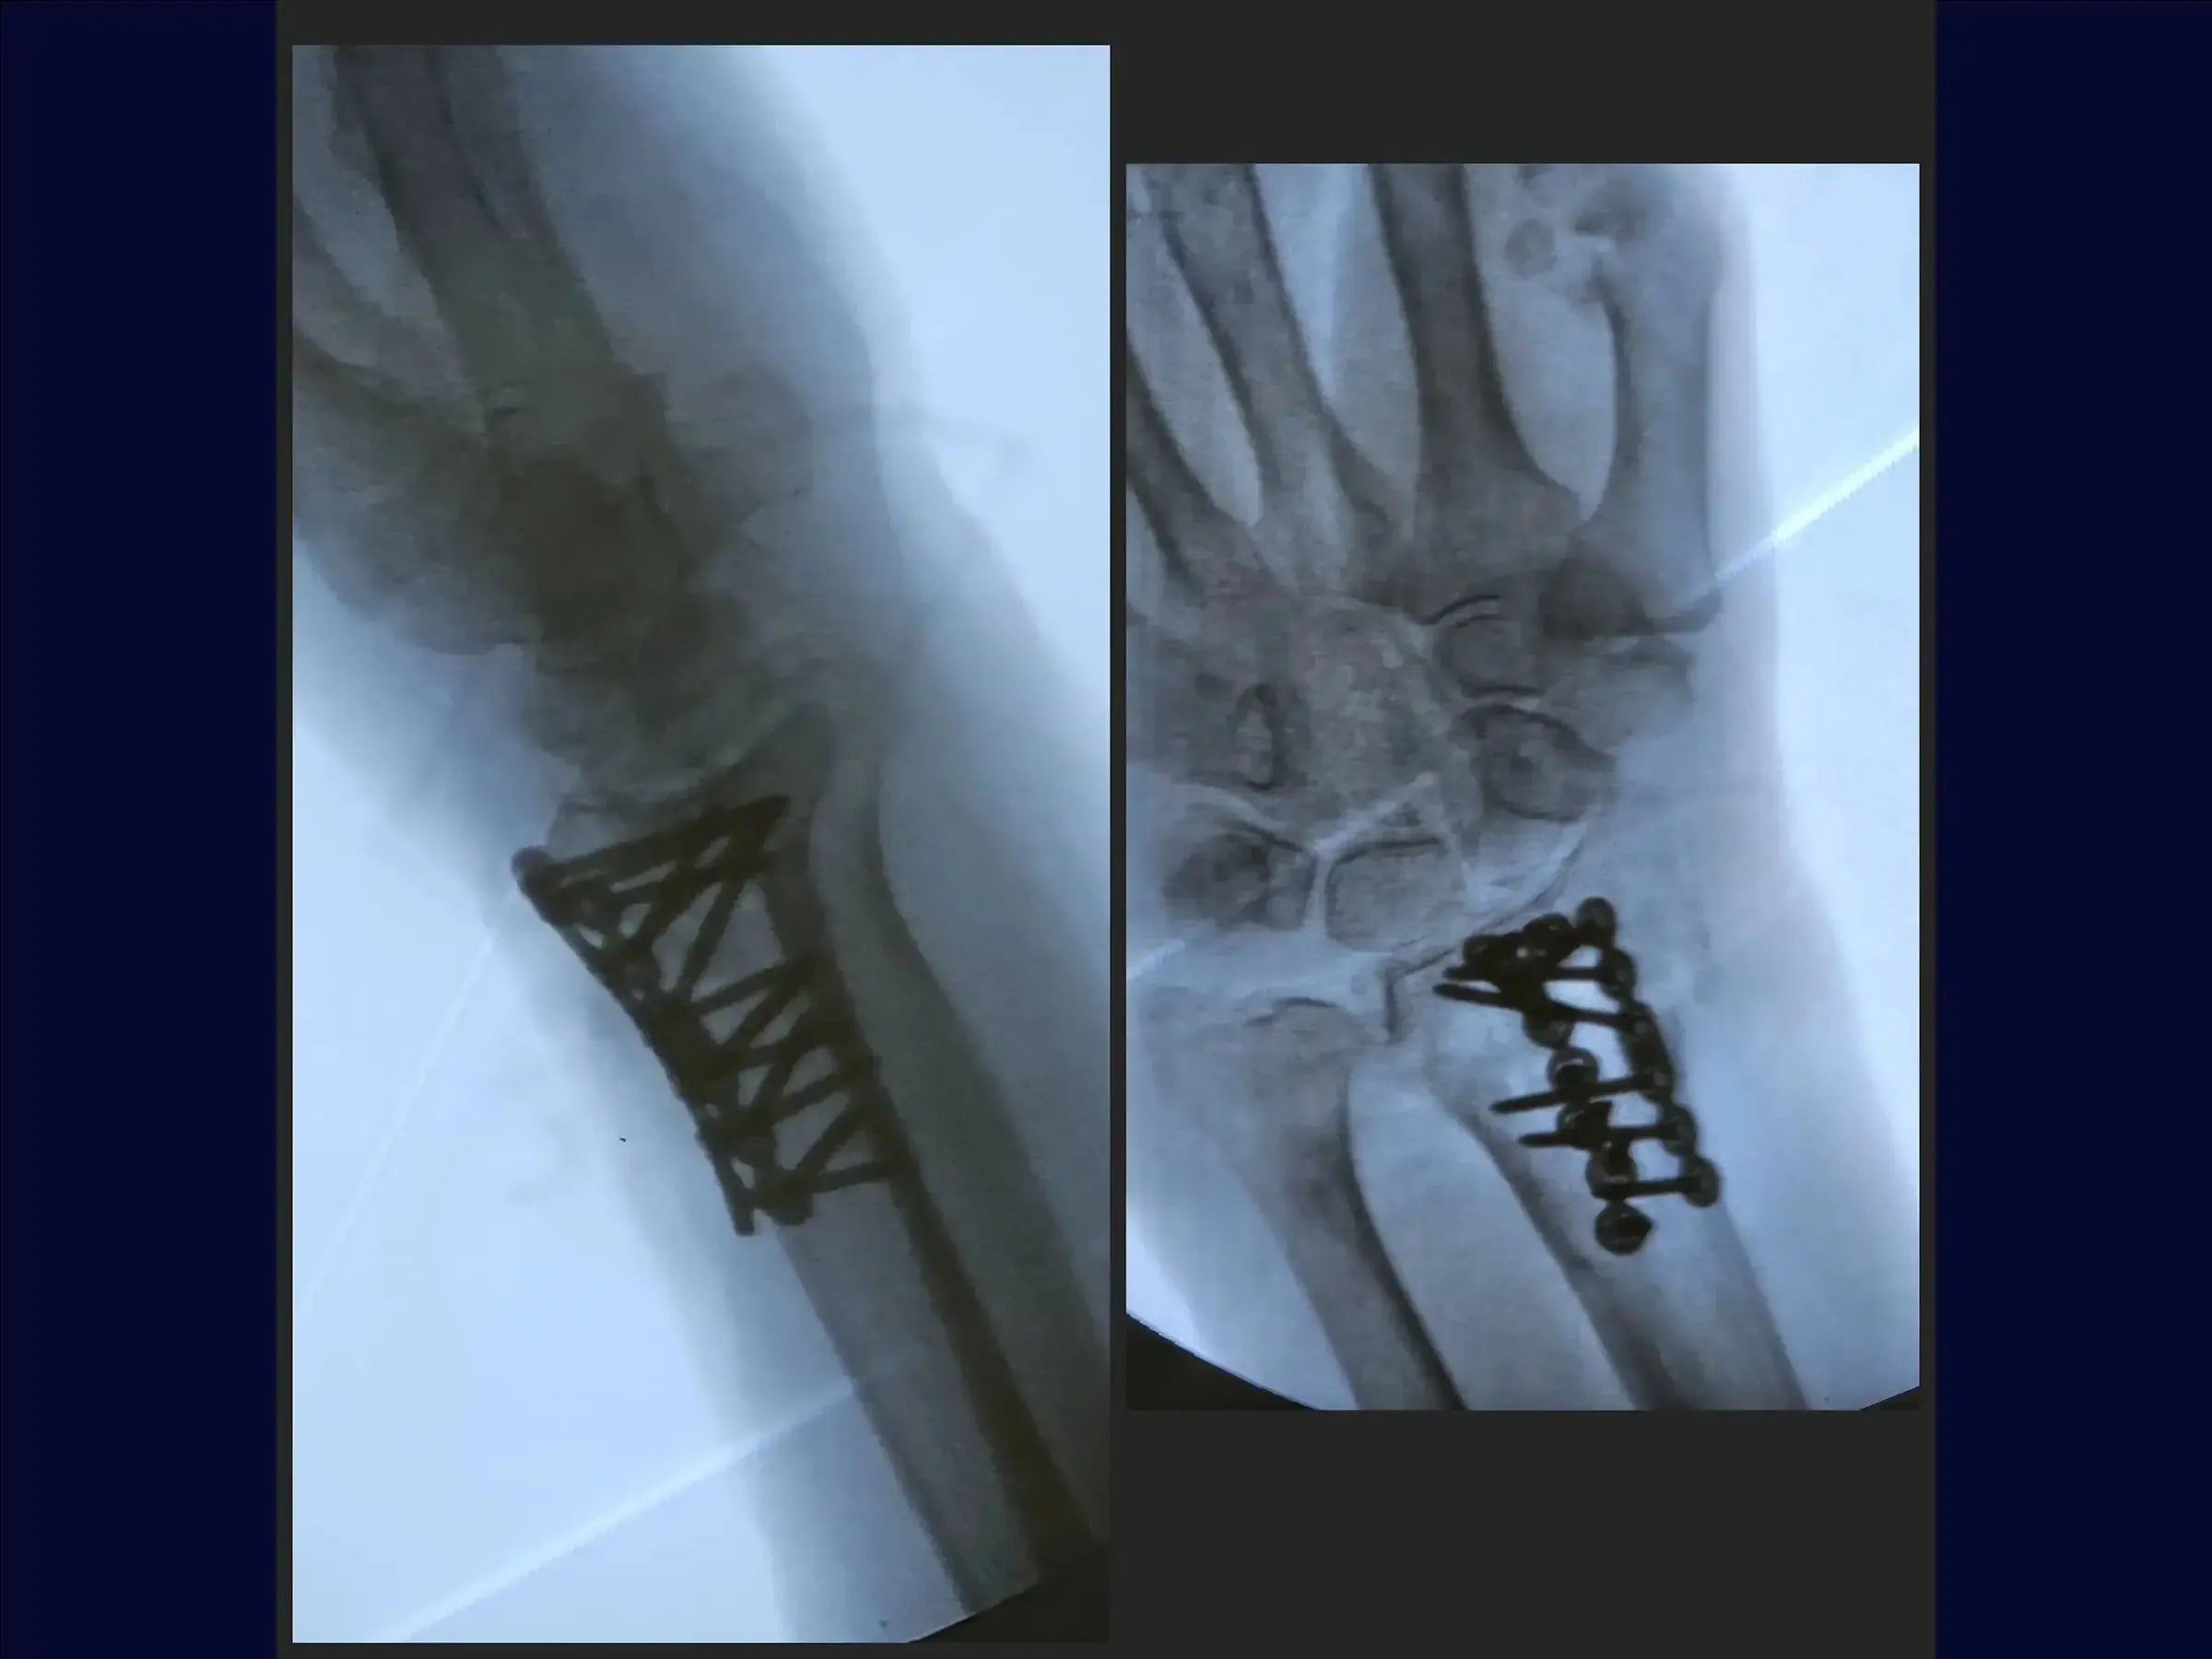

- Escolha do Implante e Redução: É apresentada a exploração da região do estiloide para identificar cominuição. O curso recomenda implantes delicados para evitar irritação tendínea. A técnica de redução indireta é demonstrada, utilizando um parafuso proximal para reduzir o fragmento através da placa, com manobras de tração se necessário.

- Fixação e Verificações: Após a placa principal, o treinamento ensina a usar uma segunda placa de baixo perfil para fragmentos dorsais destacados, visando restaurar a região articular. São ensinadas verificações para assegurar que nenhum tendão esteja sob a placa e que os orifícios não violem a articulação.

- Fechamento e Resultados: As placas são posicionadas junto ao osso, garantindo tendões livres. O treinamento cobre a avaliação da redução em termos de comprimento radial, angulação e inclinação, e a liberação imediata da mobilidade em pacientes idosos no pós-operatório. O fechamento da pele encerra o procedimento.